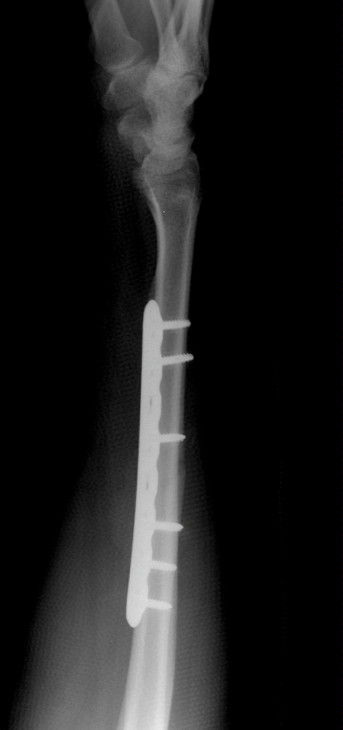

Radial Shaft Fracture Fixation with Plate